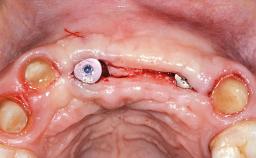

Replacement of Teeth 12 and 13 with Tissue-Level Implants

In 2001, a 48-year-old woman presented at a dental clinic with a failing fixed partial denture spanning from teeth 13 to 21. She was experiencing pain upon function, tenderness to palpation facial to tooth 13, and severe mobility of the prosthesis. Radiographic and clinical assessment revealed a subcrestal fracture of tooth 13, making its restoration unlikely. It was determined by the clinician that the tooth needed to be extracted prior to proceeding any further with dental care. After the extraction, the patient lost confidence in the progression of her treatment and sought consultation at the Center for Implant Dentistry. At her consultation visit in our clinic, an extra- and intraoral clinical examination revealed a medium lip line at full smile and an edentulous area spanning from 13 to 12 with both vertical and horizontal deficits in hard and soft tissue.

Soft Tissue Grafting Staged

Soft Tissue Anatomy Intact Defective

Soft Tissue Contour and Volume Significantly deficient